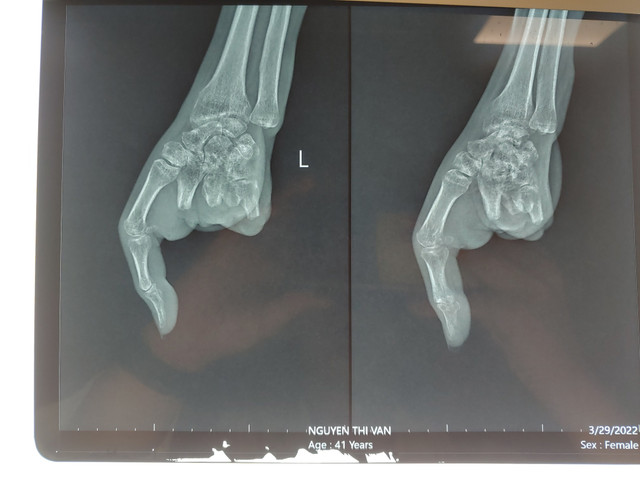

| Hình chụp X Quang trước khi nối ngón tay |

Được biết, cách đây khoảng 3 tháng, bệnh nhân Nguyễn Thị V. (SN 1981) bị máy xay thịt cuốn dập nát cả 4 ngón tay của bàn tay trái, tổn thương phức tạp. Bệnh nhân đã được nhanh chóng xử lý cấp cứu, cùng lúc thực hiện các xét nghiệm và chuyển bệnh nhân lên phòng phẫu thuật. Các ngón tay 2, 3, 4, 5 dập nát, không thể phục hồi, chỉ duy nhất còn ngón tay cái. Bác sĩ đã phẫu thuật tạo mỏm cụt từ 2 đến ngón 5 bàn tay trái.